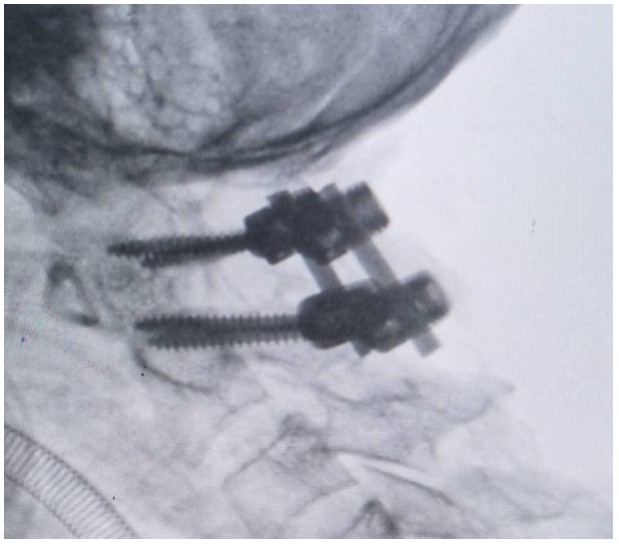

術(shù)中,錢軍博士團(tuán)隊(duì)展現(xiàn)出了非凡的勇氣和精湛的醫(yī)術(shù)。他們精心準(zhǔn)備,與手術(shù)室和麻醉科的同仁們緊密協(xié)作,以專業(yè)的技術(shù)和精確的操作,成功完成了這一高難度的手術(shù)。手術(shù)室外,譚女士的家人焦急等待,當(dāng)手術(shù)成功的消息傳來時,譚女士的家人不禁流下了感激的淚水。